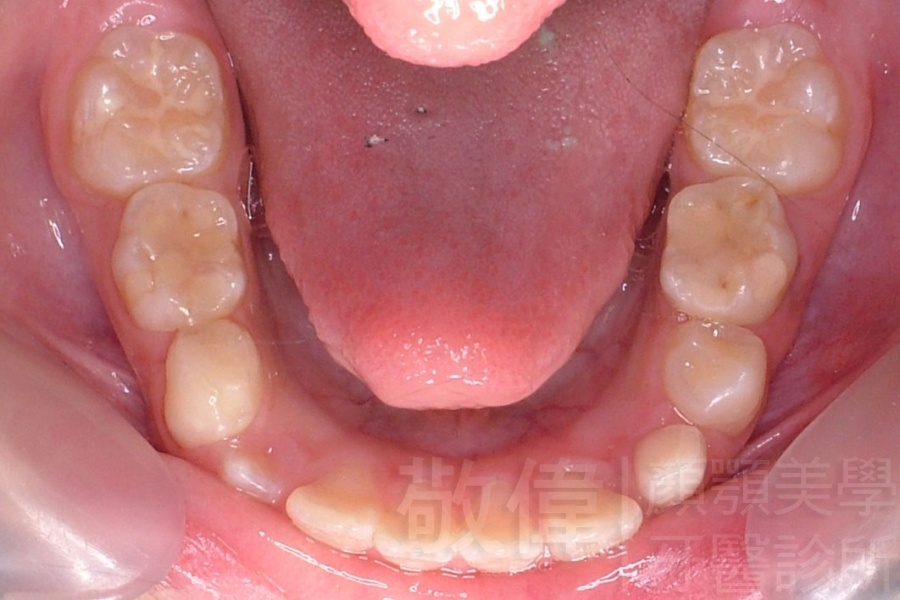

齒顏矯正/上顎暴牙且牙齒極度混亂

矯正前-上   矯正前-下

<個案說明>

上顎暴牙且牙齒極度混亂,經由矯正之後,臉型大幅度改善,牙齒的排列更加的整齊健康。相較於之前眼神充滿精神,自信心展現無遺。